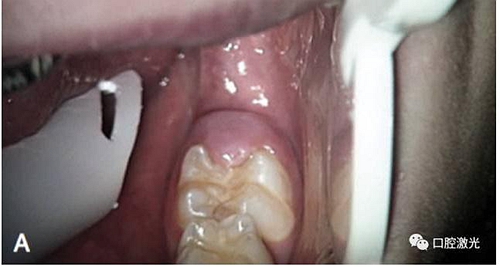

激光盲袋切除術(shù)前